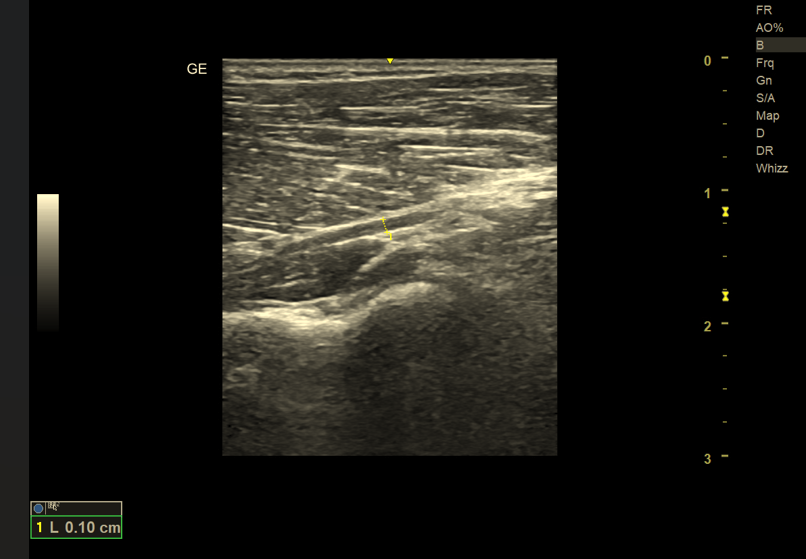

4. Zmiany relacji anatomicznych i ucisk nerwu przez struktury sąsiednie

Jedną z największych zalet ultrasonografii jest możliwość dynamicznej oceny nerwu w czasie rzeczywistym. Badanie USG umożliwia dokładną analizę relacji nerwu z sąsiadującymi strukturami, takimi jak ścięgna, mięśnie, kości czy zmiany ogniskowe.

W badaniu można uwidocznić:

• ucisk nerwu przez torbiele, gangliony, osteofity lub guzy,

• przemieszczenie nerwu podczas ruchu kończyny,

• zrosty pooperacyjne i zmiany pourazowe.

Dynamiczny charakter USG ma kluczowe znaczenie w diagnostyce niestabilności nerwu oraz zespołów uciskowych zależnych od ruchu.